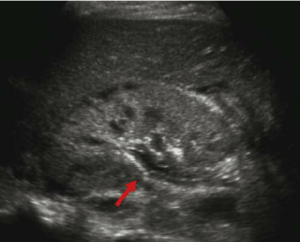

Sonographic findings

Typically you’ll see an echogenic/hyperechoic round or irregular shaped structure

usually has posterior shadowing and may display “twinkle” artifact which is a color doppler mosaic posterior to the stone (though some studies question the reliability of this technique).

Hydronephrosis can also be seen in cases of ureteral obstruction. Occasionally urothelial thickening can also be seen in cases of inflammation of the pelvocalyceal and ureteral lining and You may also see a lack of ureteral jets in cases of obstruction.